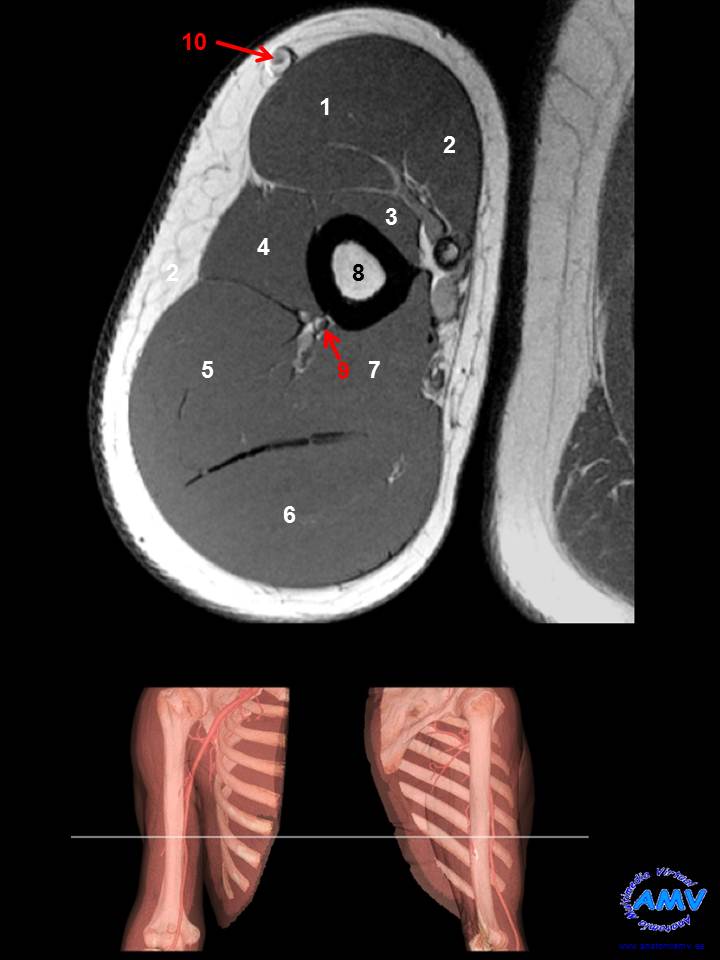

RMN Axial de Brazo

ms_rmn_04.jpgIndique que estructura se señala con el número correspondiente:

El nº 1 señala al músculo .

El nº 2 señala al músculo .

El nº 3 señala al músculo .

El nº 4 señala al músculo .

El nº 5 señala al músculo .

El nº 6 señala al músculo .

El nº 7 señala al músculo .

El nº 8 señala al hueso .

El nº 9 señala al nervio .

El nº 10 señala a la vena .